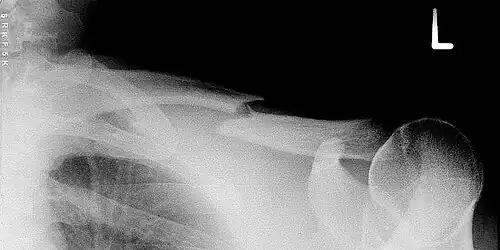

Épaule, ceinture scapulaire et humérus

Fracture de la clavicule

Fracture de clavicule (l'une des fractures les plus fréquentes)

Cette fracture est extrêmement fréquente et intéresse environ 5 % des entrants aux urgences hospitalières. Elle a lieu le plus souvent au tiers moyen de la diaphyse. Elle peut survenir chez le nouveau-né à la suite d'un accouchement difficile (fracture obstétricale).